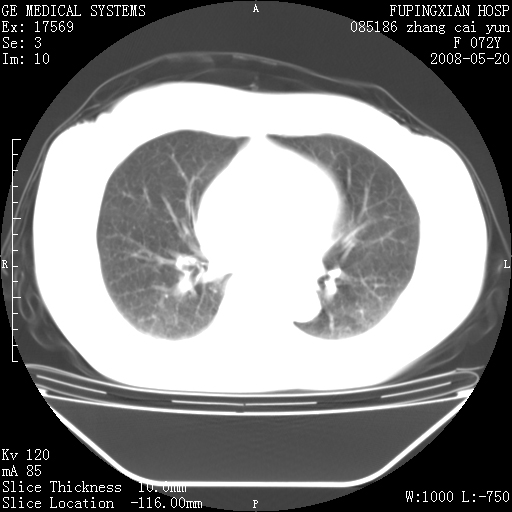

标题: CT13542:发热,咳嗽数日,经抗菌素治疗好转,请大家看排除 [打印本页]

标题: CT13542:发热,咳嗽数日,经抗菌素治疗好转,请大家看排除

右肺上叶实变影,内见支气管充气征,右上叶支气管通畅,肺门区未见软组织密度影,抗炎治疗有效,考虑炎症,建议继续抗炎治疗复查。

考虑为:右肺上叶感染性病变。建议:1)继续抗炎治疗后复查。2)必要时行纤支镜检查。

右上肺实变,间内有支气管充气征,考虑炎症,建议抗炎后复查

右肺上叶感染性病变。建议:1)继续抗炎治疗后复查。2)必要时行纤支镜检查。